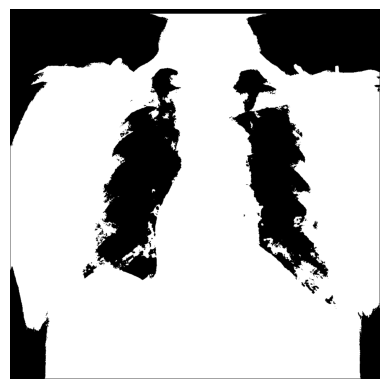

3.您可以使用 NumPy 创建不同的条件蒙版np.where()- 例如,我们只使用像素超过特定阈值的图像值:

# The threshold is "greater than 150"

# Return the original image if true, `0` otherwise

xray_image_mask_noisy = np.where(xray_image > 150, xray_image, 0)

plt.imshow(xray_image_mask_noisy, cmap="gray")

plt.axis("off")

plt.show()

# Return `1` if true, `0` otherwise

xray_image_mask_less_noisy = np.where(xray_image > 150, 1, 0)

plt.imshow(xray_image_mask_less_noisy, cmap="gray")